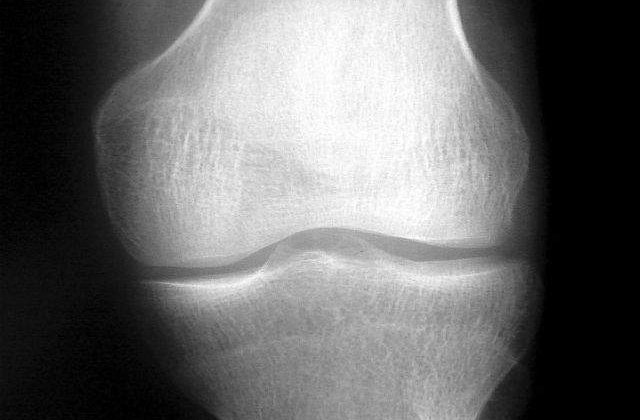

La inceputul studiului, participantii au completat cateva chestionare referitoare la durererile de genunchi de care au suferit in ultimul an si li s-au facut analize specifice - radiografii si investigatii RMN pentru genunchiul piciorului drept. Procedurile au fost repetate doi ani mai tarziu si apoi, iarasi, la zece ani de la debutul studiului. Adultii ai caror parinti au suferit operatii la genunchi tindeau sa aiba o greutate mai mare, iar in acest grup erau mai multi fumatori comparativ cu grupul de control, dar nu existau diferente intre cele doua grupuri de participanti in ceea ce priveste deteriorarile vizibile la nivelul articulatiilor genunchiului la inceputul studiului.